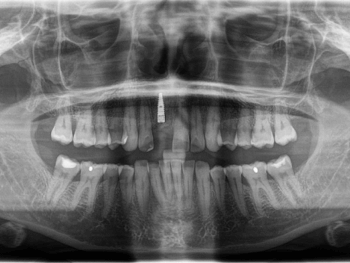

OPG nach Zahnunfall. 11 ist frakturiert.

In diesem Fall hätte eine Brückenversorgung in regio 11 viel gesunde Zahnhartsubstanz gekostet. Daher fiel die Entscheidung der Patientin auf eine Implantatkrone. Neben des wiederholten Bruchs der Interimsprothese aufgrund des Tiefbisses stellte die provisorische Versorgung aufgrund der Lage im Frontzahnbereich hohe Anforderungen. Die Patientin verfügt überdies über eine hohe Lachlinie, bei der die Gingiva komplett sichtbar ist. Um den ästhetischen Ansprüchen gerecht zu werden, war eine gründliche Planung und längerer Vorlauf erforderlich. Das Ziel war nicht nur, ein ästhetisch befriedigendes Ergebnis zu liefern, sondern dieses auch langfristig zu erhalten. Deswegen dauerte die Vorbehandlung mit Socket Preservation, PA-Behandlung, Augmentation, Implantation und Gingivaformung durch die provisorische Krone insgesamt neun Monate.